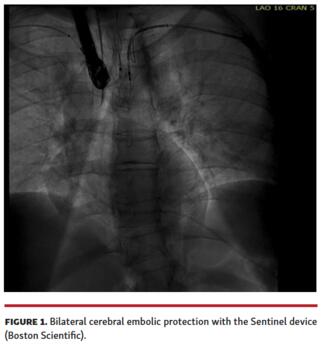

Given the proximity of the thrombus to the left subclavian, bilateral cerebral embolic protection was performed with 2 Sentinel cerebral embolic protection devices (Boston Scientific) (Figure 1). We then obtained transcaval access using standard technique (Figure 2) and a 26 Fr DrySeal sheath was placed across the retroperitoneum into the abdominal aorta. A 17 Fr cannula (Edwards Lifesciences) was placed into the contralateral vein to serve as the AngioVac return cannula. A 180° Gen 3 AngioVac catheter was then prepped in standard fashion and advanced through the 26 Fr DrySeal sheath; it was then engaged with transesophageal echocardiography guidance in the aortic thrombus, and the mobile part was successfully aspirated (Figure 3 and Video 2) with small residual clot that was adherent to the aortic wall (Video 3). The patient was discharged on therapeutic warfarin.